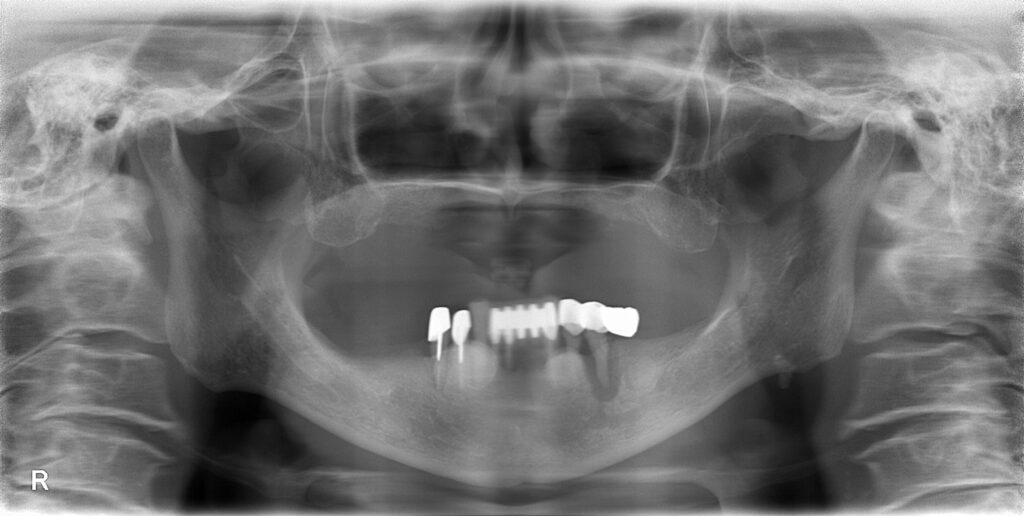

患者様のお悩みは、右下5番目の歯が割れている気がするが、かかりつけ歯科で経過観察行っているのだが改善しないので、見てほしいとのことでした。初診時レントゲン・口腔内の所見です。

【初診時】

右下5番目の歯(画面向かって一番左下の奥歯)は、レントゲン所見より真横に歯が割れているのが確認できます。残念ながら、保存は困難との診断です。

また、全体的にも検査行うと、以下のような診断になりました。

【診断】

①右下5 破折 → 抜歯

②右下2・左下5 重度歯周病 → 抜歯